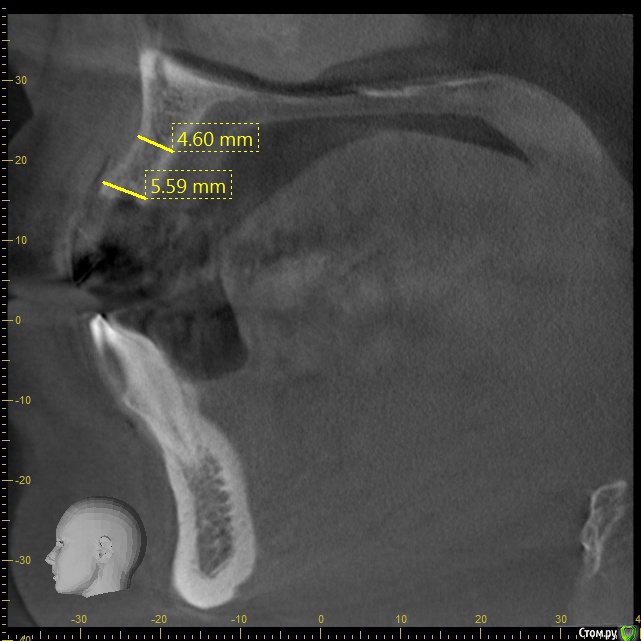

Aquarius Опубликовано 12 июля, 2017 Поделиться Опубликовано 12 июля, 2017 (изменено) Коллеги! Предстоит операция. Покрутил срезы. И призадумался. А надо ли проводить НКР , если у импланта фенестрирует апикальная половина - треть длины? Можно же сделать конверт и туда ССТ? Тем более , если вся платформа в кости. Как вы поступаете в подобных случаях? Помнится Хансер показывал кейсы с подобными вдавлениями под губой, так тот сразу за пилу и ламинат сверху. Всем спасибо заранее))http://s018.radikal.ru/i527/1707/83/ef01df8d57a3t.jpghttp://s018.radikal.ru/i510/1707/99/02e05ccff5ef.jpgИли менять направление , калибр импланта и т.д. ? Изменено 12 июля, 2017 пользователем Aquarius Ссылка на комментарий

Aquarius Опубликовано 12 июля, 2017 Автор Поделиться Опубликовано 12 июля, 2017 Спасибо! Ну хорошо, пойдет резорбция. Чем опасно это? Разумеется, все не лизируется. Биотип и так толстый. Подложен ССТ. Иньяки и не в таких ситуациях не парится. Лишняя травма. Просто рядом с имплантами есть уже установленные в другой клинике импланты и не хочется отрывать от них надкостницу. Я думаю оставить , как есть ,но так как планируется мост, то немного завалю апикальную треть орально и возьму меньший диаметр. На втором слайде - в области платформы порядка 8 мм, но в области апекса импланта - 5,5 . Ссылка на комментарий